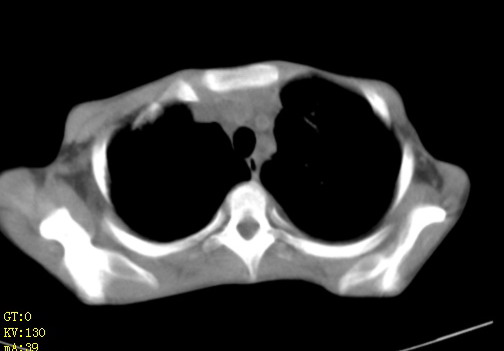

女,12岁,气促、咳嗽2天,3个月前查胸片示:两肺感染,急诊入院查ct,血常规等未检查。

双肺中下野不规则片絮状阴影,中外带明显,双侧胸腔少量积液,心影增大,心腔密度减低,隆突下及左侧气管旁见钙化淋巴结影,考虑双肺感染、心衰;建议结合临床除外h1n1并急性心衰,先心不能排除。

两肺多发片絮状模糊影,以下肺外带居多,内见支气管气像,纵膈窗未减影,两侧胸腔积液,心影增大,结合心超,支持重症肺炎,非常时期,甲型h1n1流感不排除。